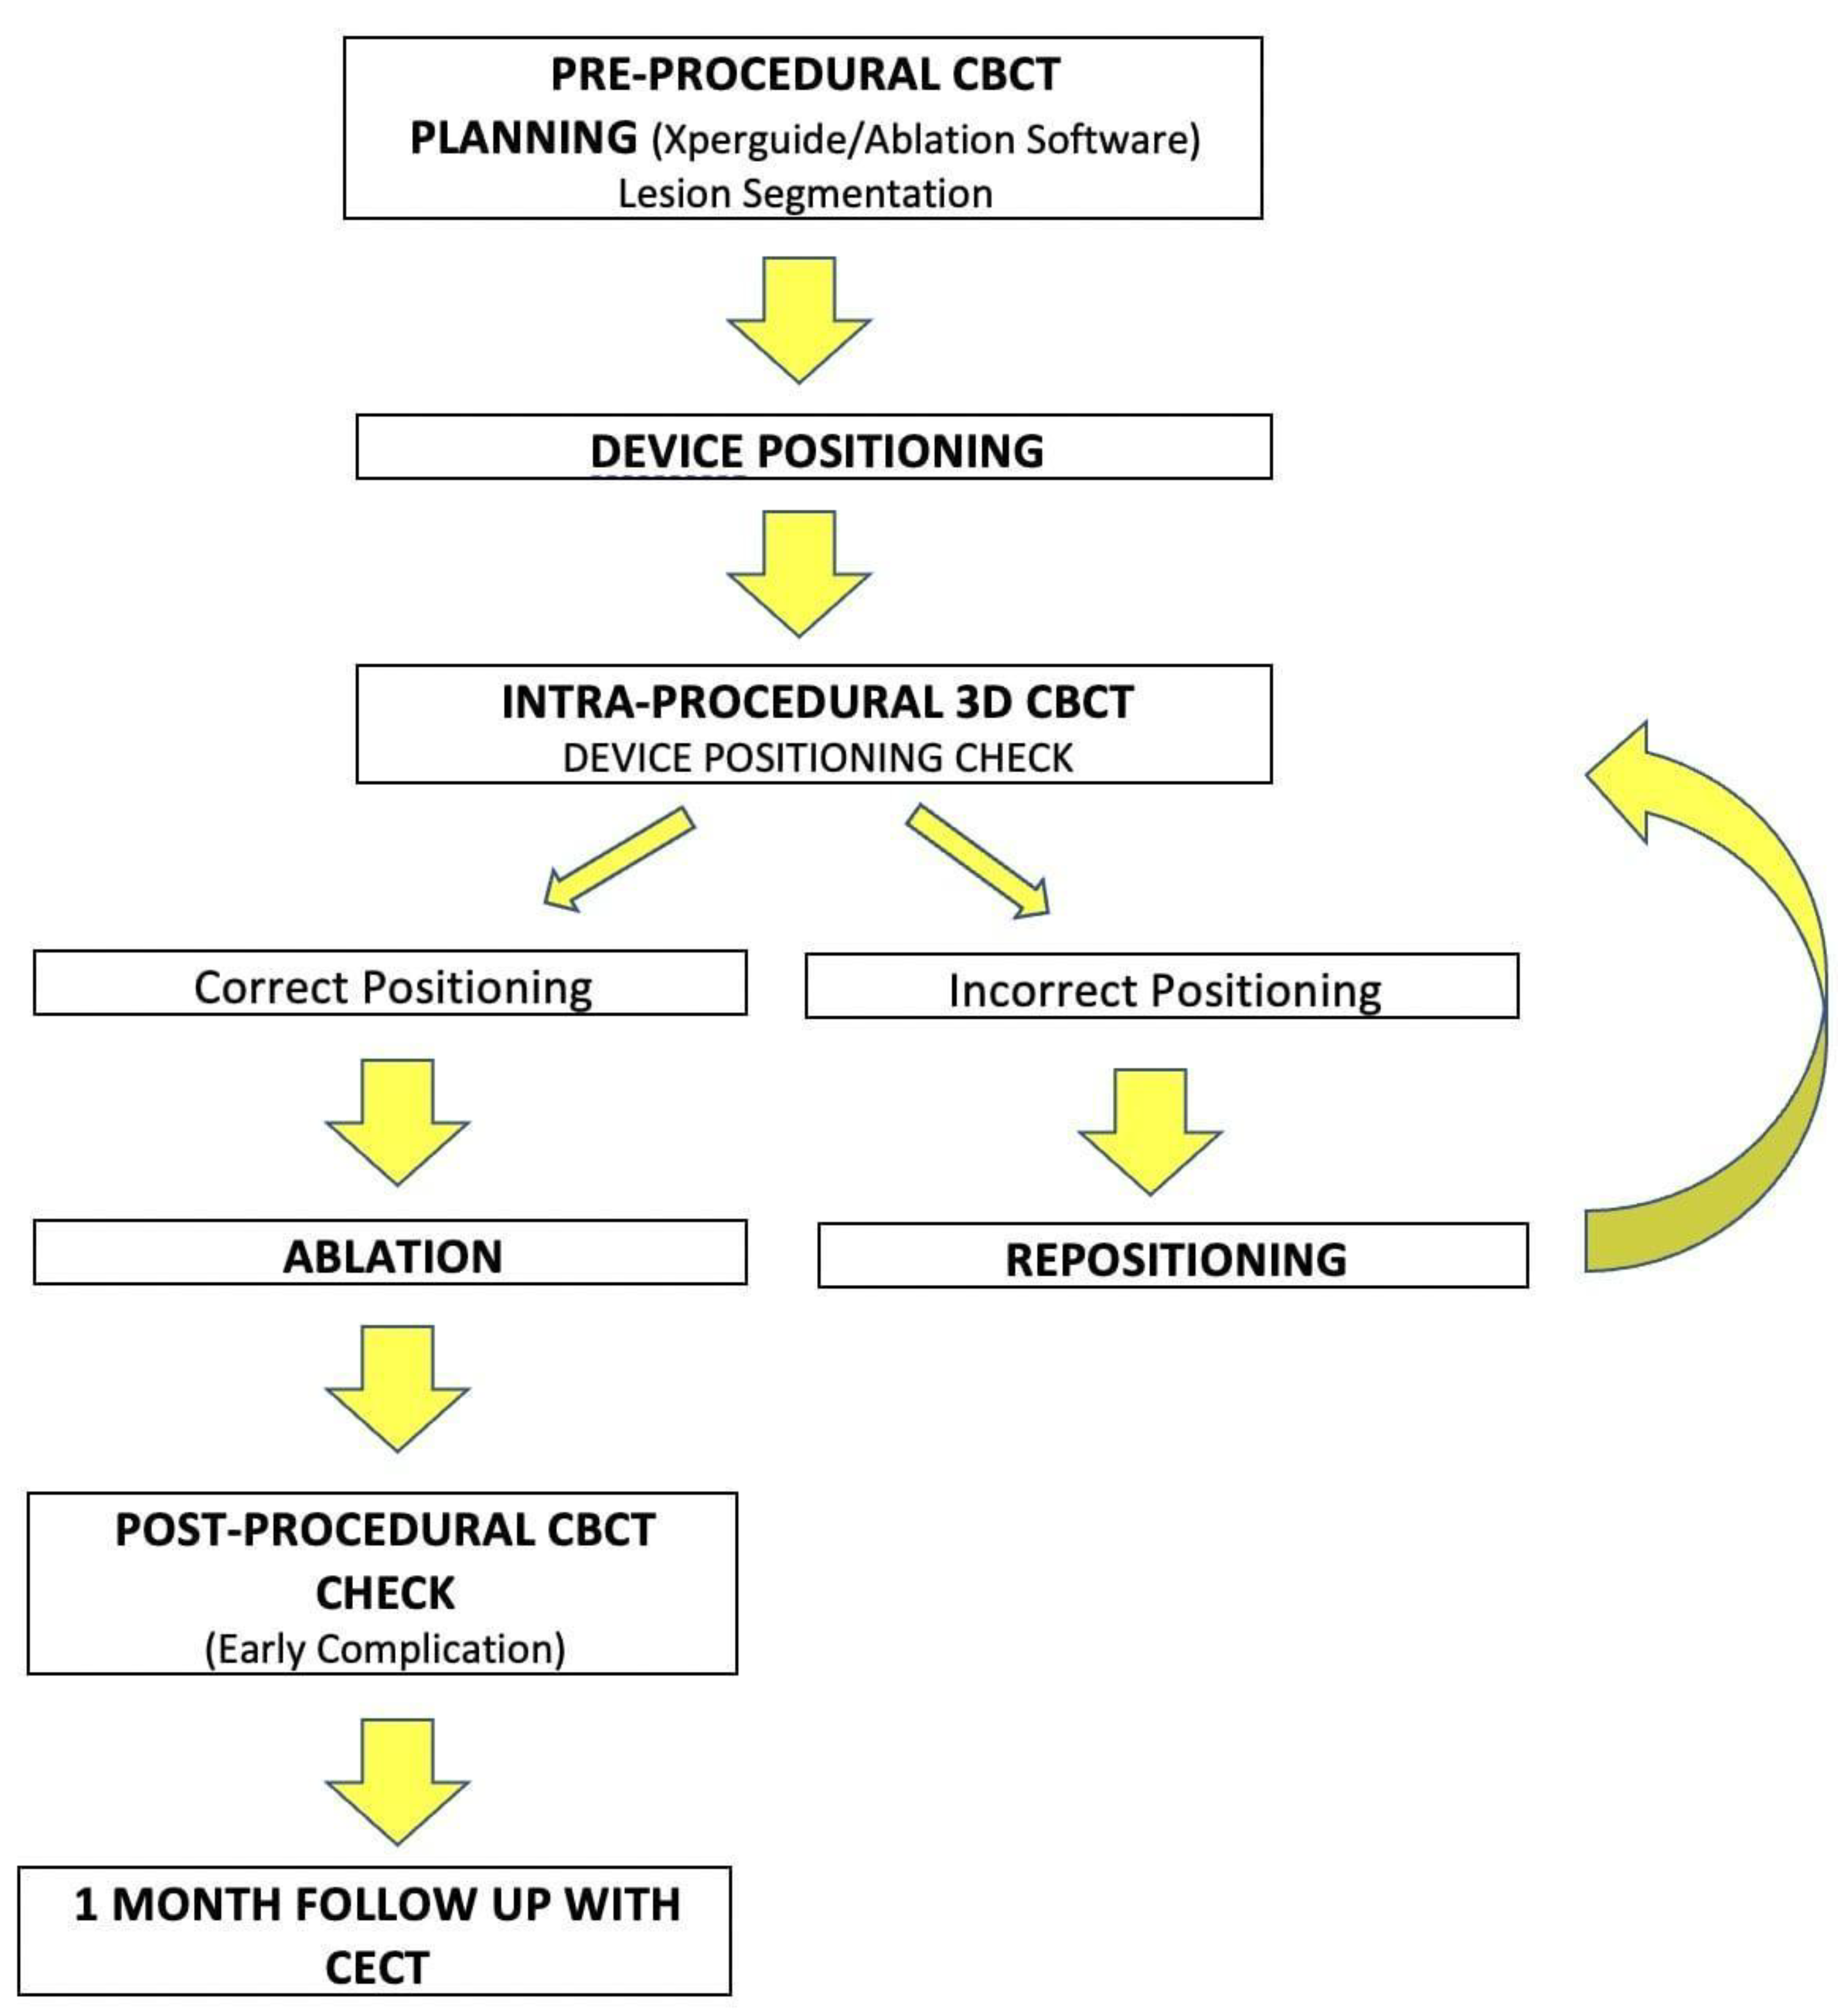

2.2. Procedure

2.3. CT Follow-Up

2.4. Outcomes